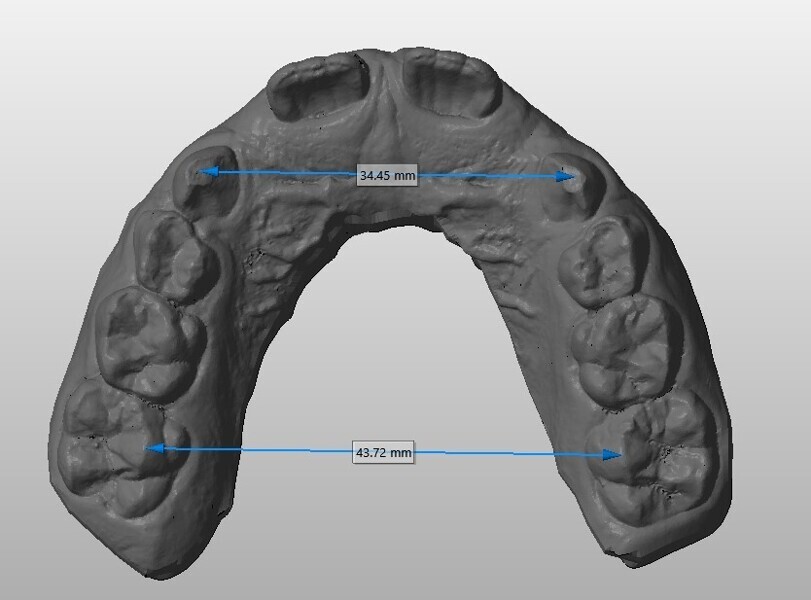

Analysis of the models in Autodesk Netfabb software (Fig. 12) showed regularisation of the arches and an increase in the maxillary inter-canine diameter of 2.61 mm and in the maxillary intermolar diameter of 2.29 mm. The superimposition of the arches at T0 and T1 (Fig. 13), performed using OnyxCeph3 (Image Instruments), was very significant and showed the shift from the initial arch shape and size to a wider shape posteriorly but with significant control of the maxillary incisor area.